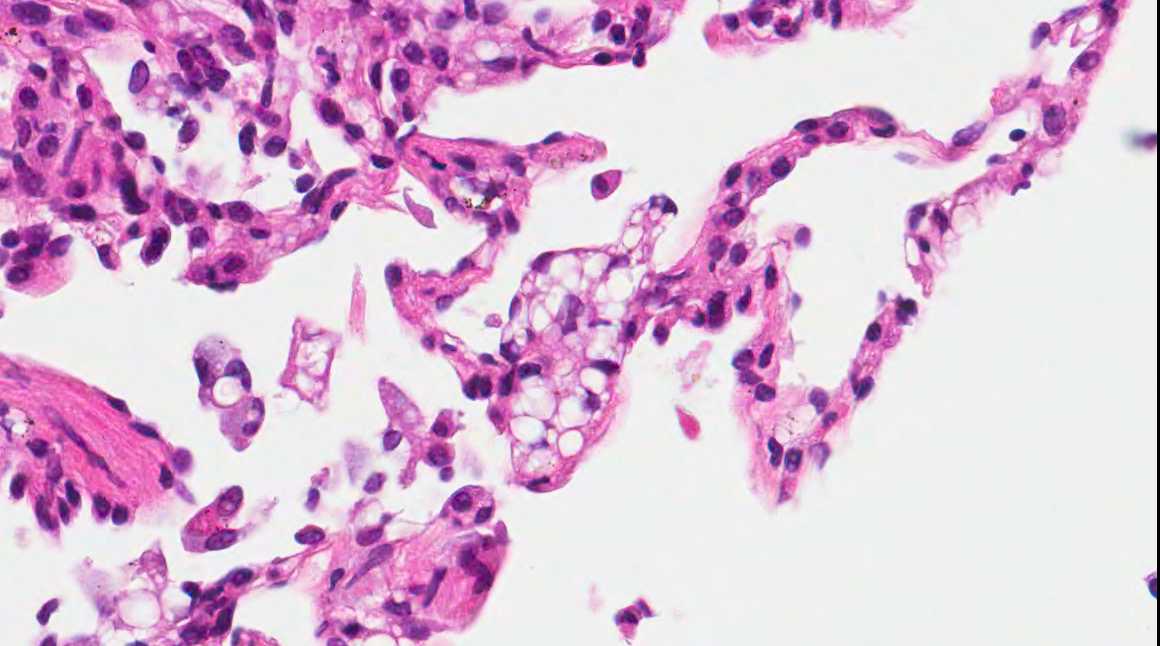

A 71 year old man with recent history of meningitis presented with recurrent episodes of pneumonia. High resolution CT scans showed crazy paving and tree in bud images. The patient underwent a transbronchial biopsy.

Micro images:

Diagnosis: Aspiration with granulomatous bronchiolitis and lipoid pneumonia

Aspiration of particulate matter, traditionally observed at autopsy, has also been described in debilitated patients, who often have a history of recurrent pneumonia, which is often unrecognized (Am J Surg Pathol 2007;31:752, Am J Surg Pathol 2010;34:1456). It usually (88%) shows bronchiolitis obliterans organizing pneumonia, often with multinucleated giant cells, acute bronchopneumonia / bronchiolitis or suppurative granulomas. Foreign material is usually but not always present (Am J Surg Pathol 2011;35:426).

The differential diagnosis of pulmonary granulomatous inflammation is broad and requires special stains, culture and clinical correlation (Ann Diagn Pathol 2003;7:127, Histopathology 2007;50:289).

Lipoid pneumonia is often an incidental postmortem finding associated with debilitating disease. The lipid may be exogenous (from nasal sprays or inhalation of other lipid containing substances) or endogenous (bronchial obstruction).

A 71 year old man with recent history of meningitis presented with recurrent episodes of pneumonia. High resolution CT scans showed crazy paving and tree in bud images. The patient underwent a transbronchial biopsy.

Micro images:

Diagnosis: Aspiration with granulomatous bronchiolitis and lipoid pneumonia

Aspiration of particulate matter, traditionally observed at autopsy, has also been described in debilitated patients, who often have a history of recurrent pneumonia, which is often unrecognized (Am J Surg Pathol 2007;31:752, Am J Surg Pathol 2010;34:1456). It usually (88%) shows bronchiolitis obliterans organizing pneumonia, often with multinucleated giant cells, acute bronchopneumonia / bronchiolitis or suppurative granulomas. Foreign material is usually but not always present (Am J Surg Pathol 2011;35:426).

The differential diagnosis of pulmonary granulomatous inflammation is broad and requires special stains, culture and clinical correlation (Ann Diagn Pathol 2003;7:127, Histopathology 2007;50:289).

Lipoid pneumonia is often an incidental postmortem finding associated with debilitating disease. The lipid may be exogenous (from nasal sprays or inhalation of other lipid containing substances) or endogenous (bronchial obstruction).